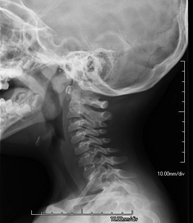

Técnica mediante la cual, utilizando rayos X, se obtienen imágenes del cavum para su estudio. Indicaciones: dificultad respiratoria, anginas de repetición en lactantes y niños. - RX Columna cervical

Técnica mediante la cual, utilizando rayos X, se obtienen imágenes de la columna cervical para su estudio. Indicaciones: traumatismo, contractura cervical, dolor articular. - RX Huesos propios nasales

- Cervical spine X-ray

This technique uses X-ray rendered imaging for examining the cervical spine. Indicated for: trauma, cervical pain.